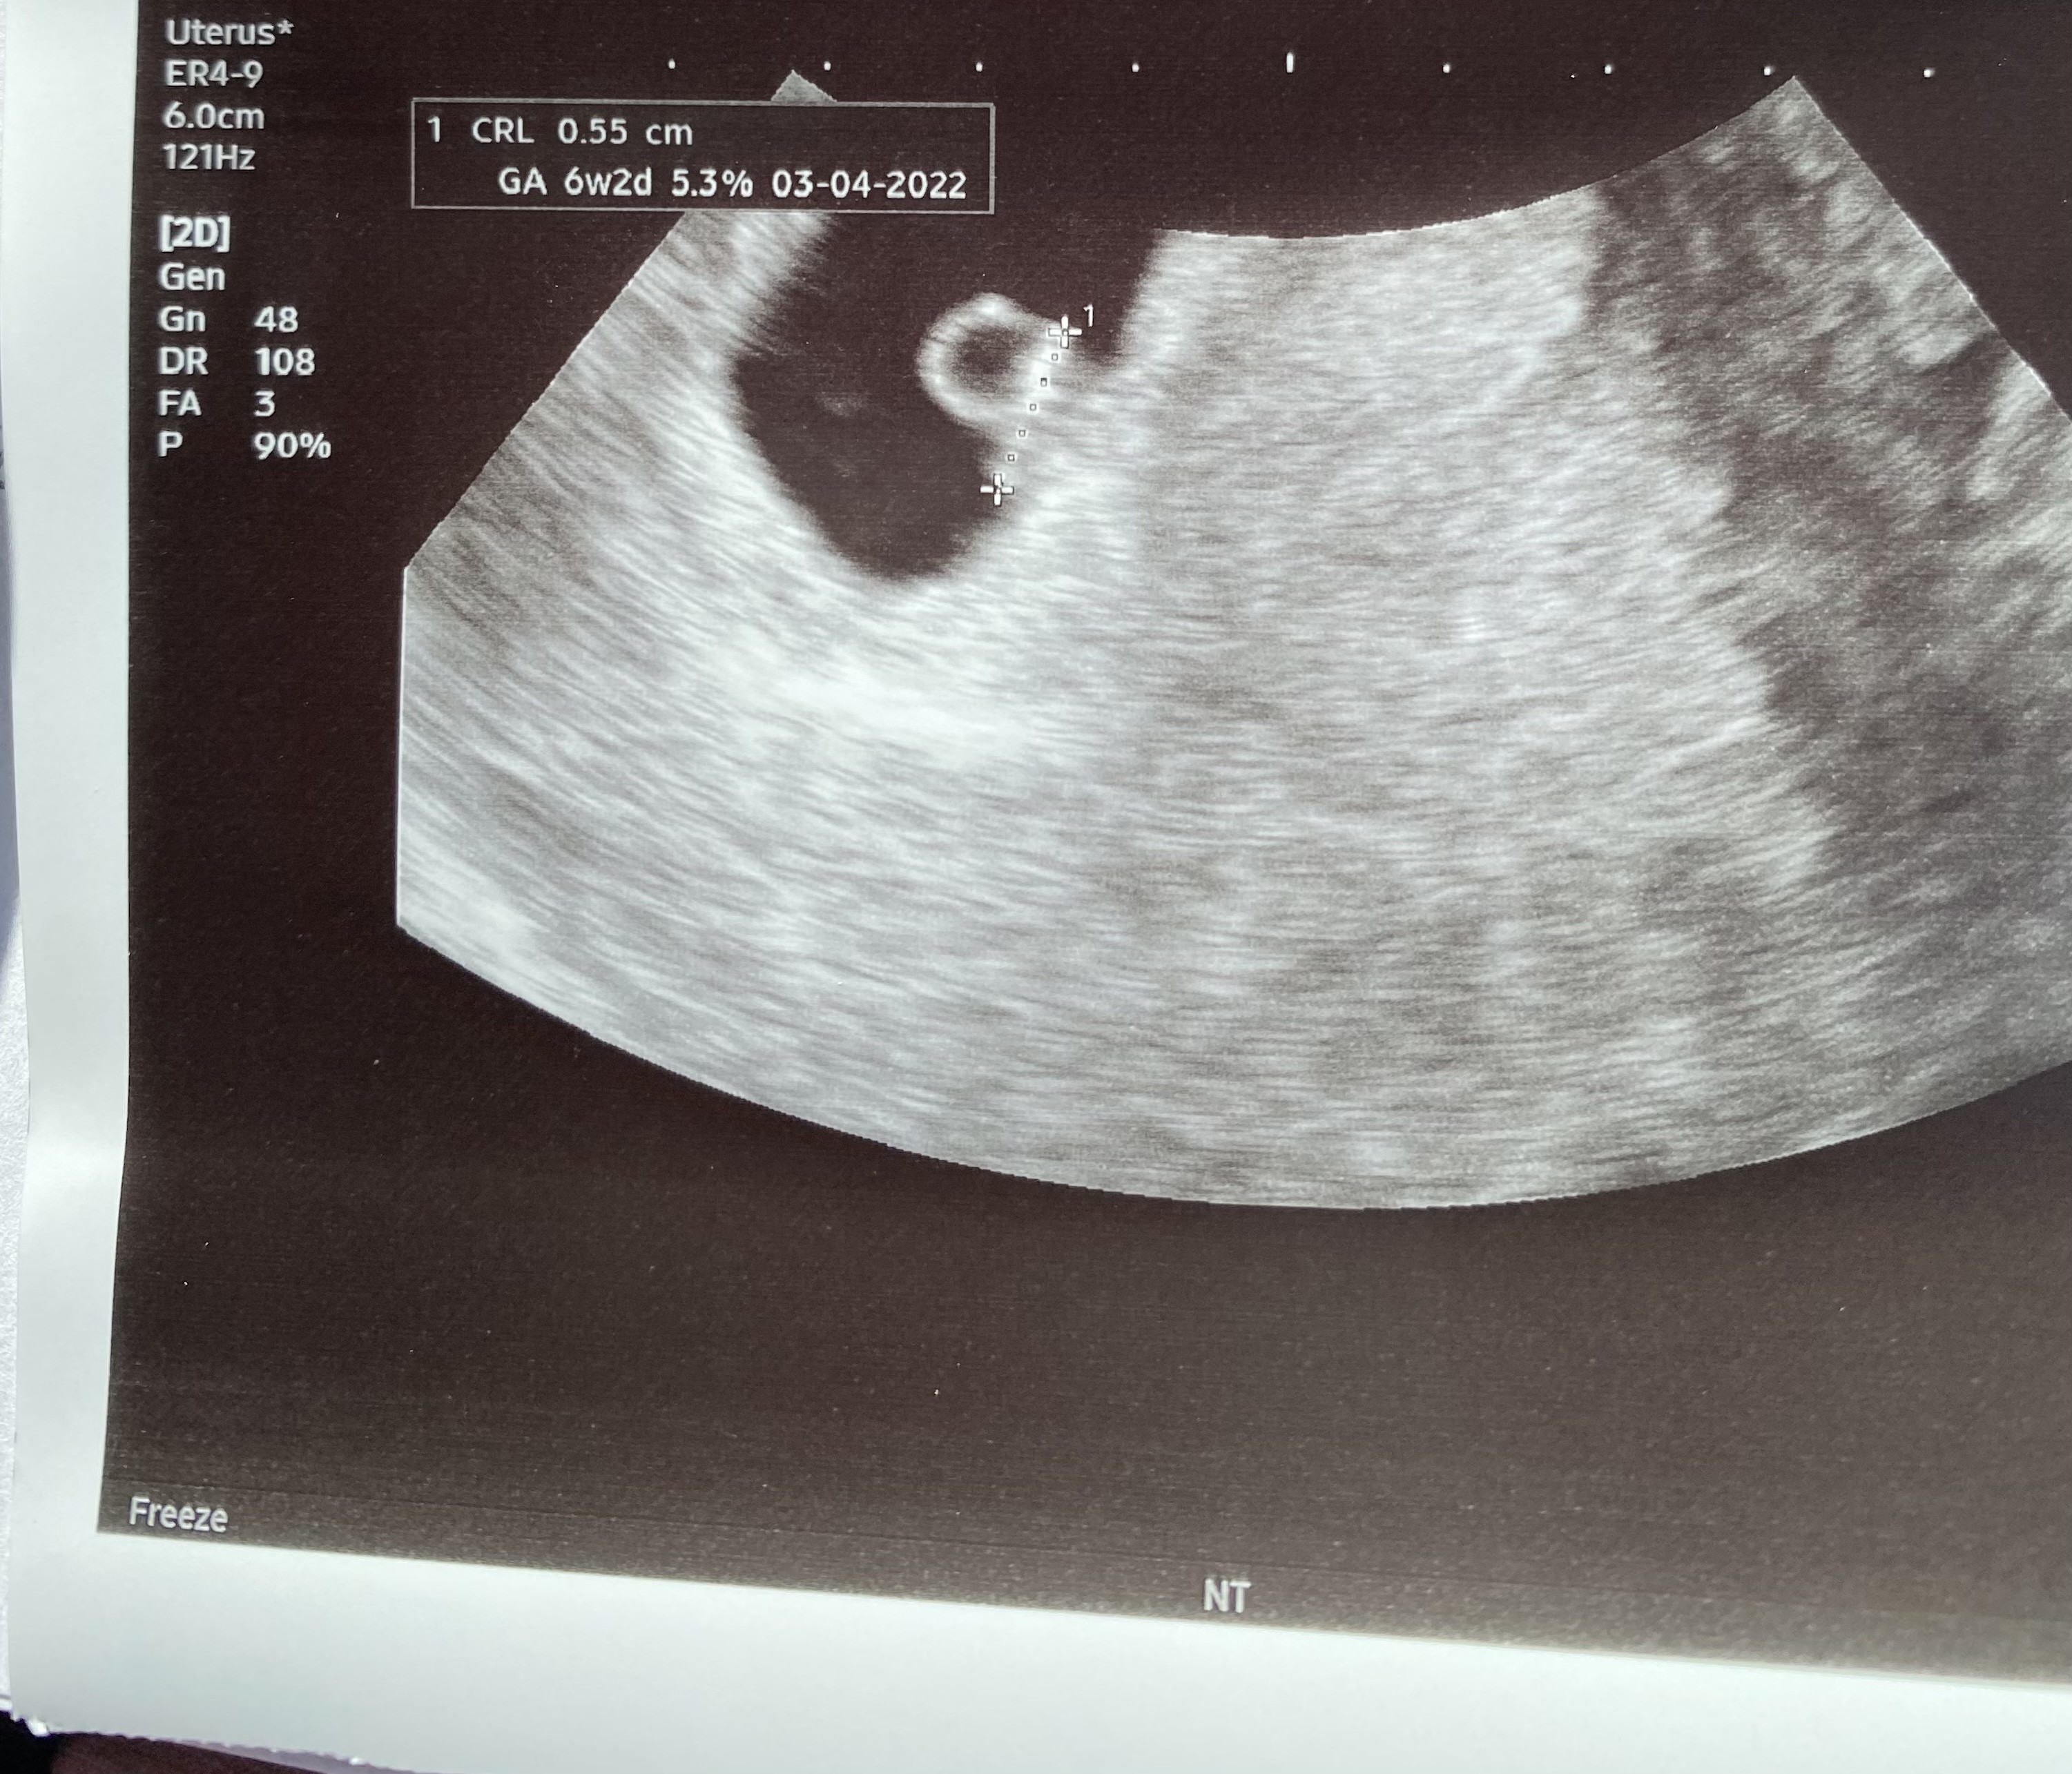

Jestem juz po pierwszej wizycie i wszystko dobrze. Termin 03.04.2022 🙂 Było widać ♥️ Przy ostatniej ciazy się nie doczekałam, wiec się bardzo wzruszyłam jak je zobaczyłam.

Załączniki

• B7CB934E-3CE0-4962-9016-9DB55CD7EA24.jpeg

B7CB934E-3CE0-4962-9016-9DB55CD7EA24.jpeg

1,3 MB · Wyświetleń: 119

Jakie było tętno zarodka? [emoji846] też dzisiaj miałam usg, CRL podobnie jak u Ciebie, serduszko biło ale trochę się obawiam że tętno jest za niskie - pewnie znowu się niepotrzebnie zamartwiam [emoji2]